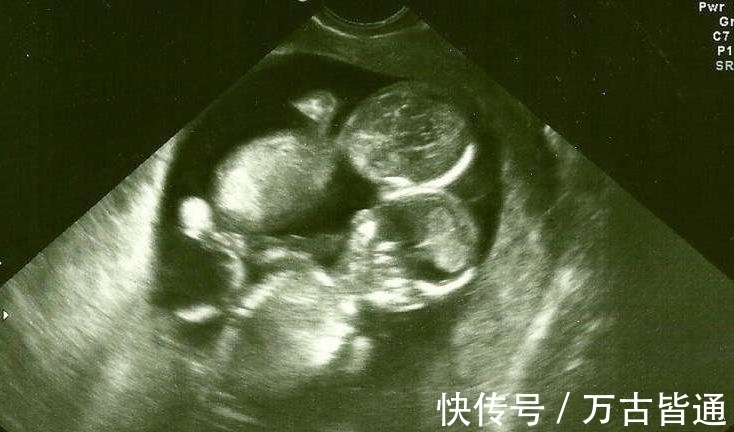

怀孕的妈妈都希望自己的婴儿健康!假如妈妈们事先知道生产时可能发生意外,你猜猜她们会不会生下来?有一位陈姓母亲,在照超音波时,知道了肚子里的双胞胎竟然是连体婴!她面临了很艰难的选择,看下去!

陈女太久没有来月经,就去医院检查,医生说:「你怀孕了,而且是双胞胎!」可是医生接下来的话让她沉默了很久,她从医生口中,知道宝宝竟然是「连体婴」!

医生非常惊讶!他很确定之前他在照超音波时,2个婴儿是连在一起的,後来医生猜测,可能当初他照射照音波时,2个宝宝紧紧抱住,才会误会!